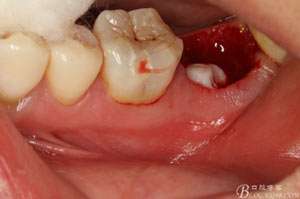

圖9.清理牙槽窩過(guò)后。多生牙的牙冠暴露在牙槽窩內(nèi)。

病例二:

圖1.患者自述右側(cè)下后牙牙齦紅腫,咀嚼不適。術(shù)前口內(nèi)像:37頰側(cè)牙齦紅腫

圖3.拔除47后的牙槽窩影像:

圖4.術(shù)后拔除的牙根: